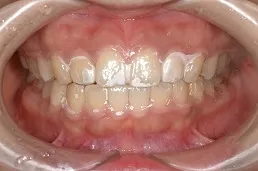

従来のブラケット(金属の装置)を歯に付ける矯正方法とは異なる、透明なマウスピース型の矯正装置です。

マウスピース型矯正歯科装置は、透明なアライナーというマウスピースを使用し、少しづつ歯を移動します。

いつでも取り外しが可能なので、食事もおいしくいただくことができ、ブラッシングもキレイにできるので、お口の中を清潔に保つことが出来ます。